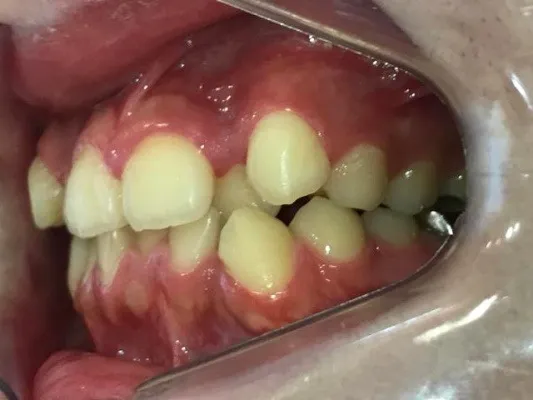

今回は下の前歯が1本ない場合の矯正治療についてご紹介いたします。